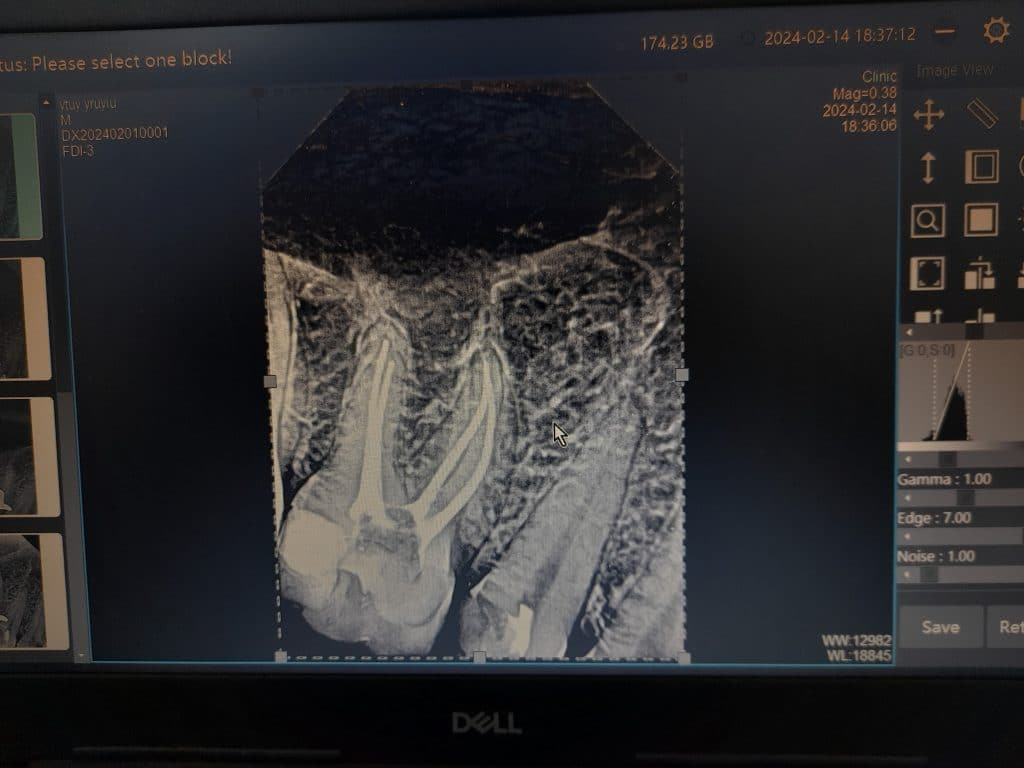

Cold test, clinical examination and Radiographs for diagnosis

Tooth 35 diagnosis: irreversible pulpitis

Tooth 36 diagnosis: necrotic pulp and acute apical periodontitis

Root canal treatment, lateral condensation obturation, resin based sealer. Tooth 36